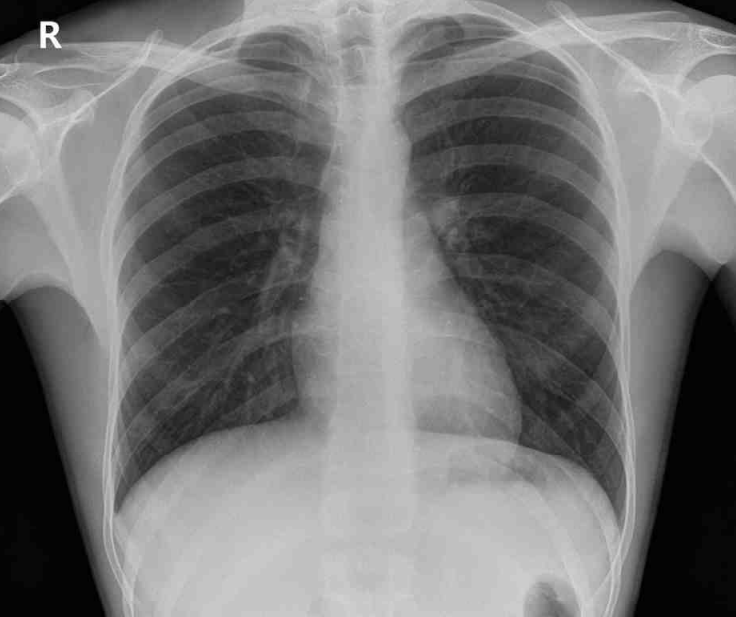

36세 남자가 30분 전부터 갑자기 가슴이 조인다며 응급실에 왔다. 만원버스를 타고 퇴근하던 중에 갑자기 숨이 멎을 것 같고, 숨을 쉬어도 막힌 듯 가슴이 답답하며, 어지럽고 식은땀이 났다. 지난 1개월 동안 이와 유사한 증상이 4~5회 있었으나 모두 수 분 안에 자연적으로 회복되었다고 한다. 응급실에서 시행한 혈액검사 결과는 다음과 같다. 가슴 X선사진과 심전도이다. 치료는?

CXR: No remarkable findings

• CXR과 ECG상 특이 사항이 없고, 트로포닌 I도 정상이므로 흉부 불쾌감을 일으킬 수 있거나 공황발작과 감별해야 할 심혈관계 질환(관상동맥질환, 특발성 심근병증, 승모판 탈출증 등)을 배제할 수 있다.